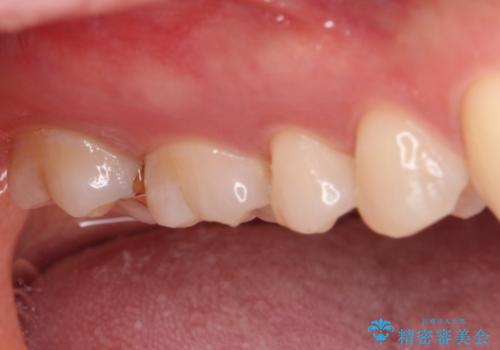

- 奥歯の銀歯と虫歯を気にして来院された患者様です。

下顎は口を開けたときに目立つためセラミックインレーに、上顎奥歯は機能面を優先してゴールドインレーにて修復治療を行うこととしました。

機能面を優先すると、PGAインレー(ゴールドインレー)による修復治療やPGAクラウンによる補綴治療が望ましいのですが、笑ったときに見えている銀歯がどうしても気なってしまうとのことで、目立ってしまう奥歯はセラミックインレーやセラミッククラウンを装着することとしました。

見た目を気にすることなくむし歯治療を行うことができ、患者様に大変満足していただきました。